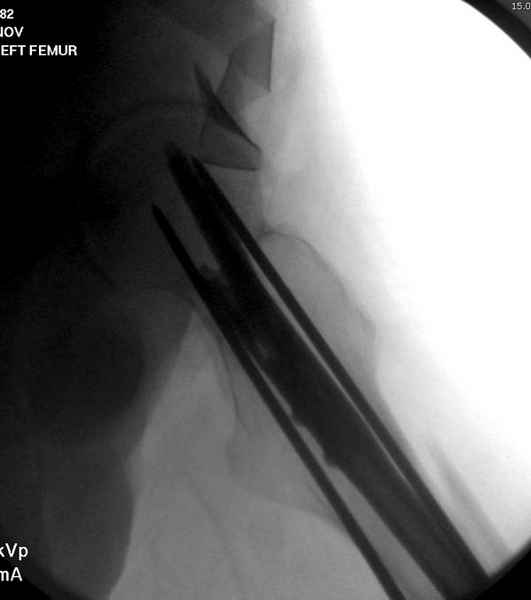

Среди русскоговорящих коллег Ортофорум стал одним из мест, где многие из нас черпают знания для решения своих ежедневных проблем в виде практических советов и обмена опытом. Кроме таких советов, Ортофорум стал источником новых познаний среди ортопедов, особенно по редко встречающимся состояниям в ортопедии. Продолжая традицию, я хотел бы представить редко встречающий случай перелома бедра у больного с гемофилией. Больному 42, гемофилия типа А, из истории упал с высоты около 1,5 метра, переправлен из другой больницы. По происхождению мексиканец, 10 лет назад по поводу артроза пр. коленного сустава в Мексике сделано протезирование, которое закончилось ампутацией выше коленного сустава. При поступлении бедро напряженное, сосудистых и неврологических расстройств нет. На рентгенограмме оскольчатый перелом бедра с вовлечением проксимальной спирали в шейку бедра. Хотели бы знать тактику ведения подобных больных и на что надо обратить внимание? Djoldas Kuldjanov, MD Department of Orthopedic Surgery St. Louis University Medical Center

Учитывая, что случай ургентный, больной поступил вечером, не стали делать вытяжение и срочно провели операцию по фиксации перелома бедра антеградным штифтом Versa Nail от DePuy.

Для профилактики дальнейшего раскола в шейке предварительно во время проксимального рассверливания спереди и сзади провели временные спицы, которые в дальнейшем были заменены на шурупы (miss nail method)